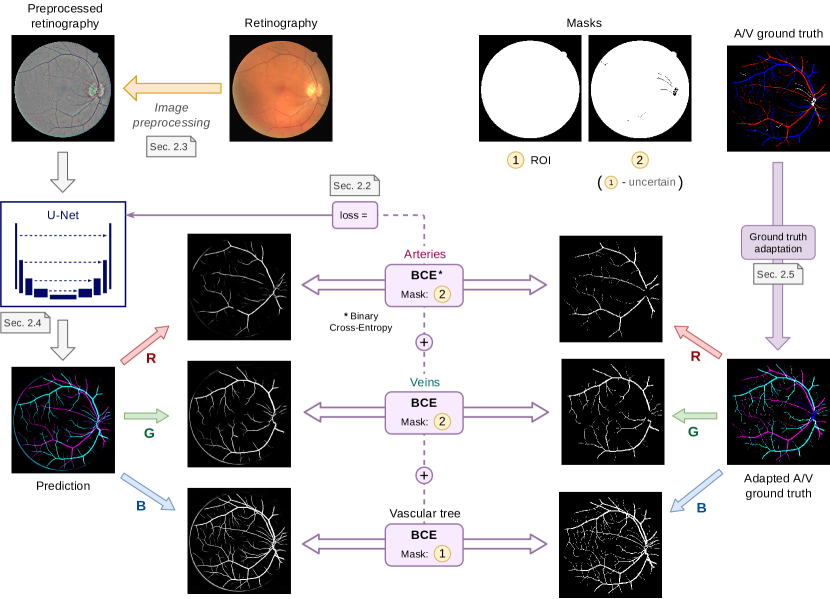

Our proposed approach for SSCAV is depicted in Figure 3.

To both segment and classify the retinal vessels, we decompose the SSCAV problem into three different tasks: arteries segmentation, veins segmentation and vessels segmentation. This multi-segmentation (MS) approach is in line with the dual nature of the retinal vascular tree, where arteries and veins individually spread throughout the retina and intersect frequently at different points. Moreover, following this approach, the three continuous vascular tree segmentation maps (arteries, veins and all the vessels) are also directly provided by the neural network.

In this case, the network output consists of 3 independent channels (see Figure 3). Each channel contains the predicted probability map for one of the structures of interest: arteries, veins and vessels. The total loss is computed as the sum of the individual losses for each structure, each being calculated as the Binary Cross-Entropy (BCE) between the manually annotated segmentation mask of the structure and the corresponding predicted probability map. Mathematically, the “Binary Cross-Entropy by 3” (BCE3) loss is defined as

where r is the input retinography, and the network output and the ground truth for class and is the set of all the pixels within a class-specific ROI mask. The class-specific ROI mask for the vessels class is the retinal ROI, and it is equivalent to the used in Equation 1. Differently, for the artery and vein classes, the ROI mask is computed as the retinal ROI minus the vessel pixels of uncertain class, as labelled by the experts in the ground truth. Examples of these ROI masks are represented in Figure 3.

Notice that avoiding the uncertain pixels in the artery and vein segmentation losses (i.e. to mask them for the computation of the loss), and not in the vascular segmentation one, allows the system two things: first, to freely assign those pixels to artery or vein classes (as in the case of the traditional approach), and second, to simultaneously receive feedback for those pixels in the vascular segmentation subtask. Consequently, the network receives feedback for every pixel inside the ROI.

In addition to this feature, it is also relevant to note that, in this case, the “uncertain” class does not include the vessel crossings, unlike the “uncertain or crossing” class defined in the traditional approach. Instead, in this approach, the vessel crossings are encoded as the superposition of the artery and vein segmentation maps, which should be both indicating positive class for these pixels. In order to do that, the ground truth for each class should be adapted to the output of the network and these restrictions. This can be achieved by considering the vessel crossing regions as positives in both artery and vein segmentation maps, and combining these two maps with the uncertain vessel regions to obtain the vascular tree segmentation map. An example of such an adapted ground truth is shown in Figure 3. Additionally, this setting allows to detect vessel crossings through the intersection (product) of the predicted arteries and veins segmentation masks.